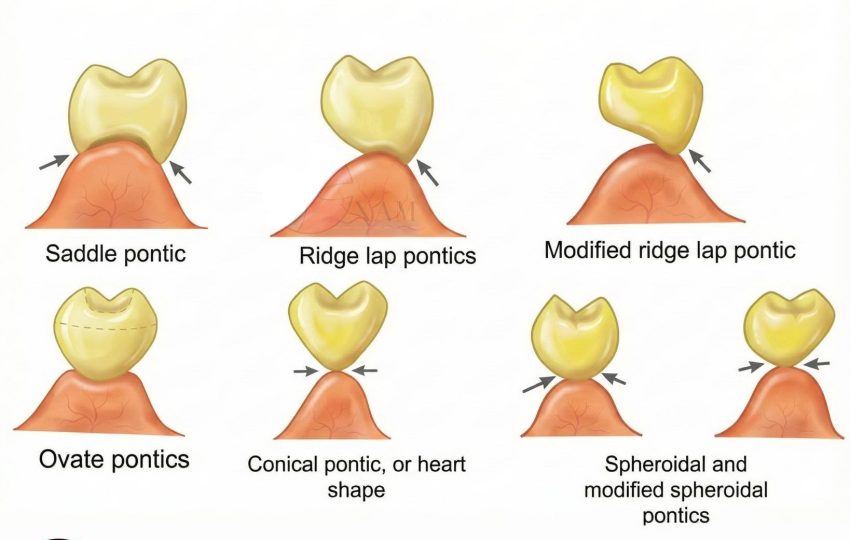

Răng giả nhịp cầu dạng yên ngựa (Saddle Pontic)

- Tiếp xúc: Mặt đáy răng giả có dạng lõm, phủ kín và ôm trọn sống hàm còn lại, tương tự như yên ngựa đặt trên lưng ngựa.

- Đặc điểm: Tạo ra vùng tiếp xúc rộng và lớn với niêm mạc ở cả mặt ngoài và mặt trong của sống hàm.

- Thực tế trong lâm sàng: Nhịp cầu loại này có diện tiếp xúc với niêm mạc quá rộng. Dù nhìn bên ngoài rất thẩm mỹ vì ôm sát sống hàm, nhưng nó tạo ra một “vùng chết” không thể làm sạch bằng bàn chải hay chỉ nha khoa dẫn đến vi khuẩn tích tụ dưới đáy nhịp cầu sẽ gây viêm nướu mạn tính, hôi miệng và tệ nhất là tiêu xương ổ răng của các răng trụ. Mình khuyên anh em nên tránh nhịp cầu loại này nếu không muốn bệnh nhân quay lại bắt đền vì cầu răng hôi và viêm..

Răng giả nhịp cầu dạng ôm sống hàm (Ridge Lap Pontic)

- Tiếp xúc: Mặt đáy răng giả phủ lên sống hàm ở phía ngoài (má/môi) nhưng được cắt bỏ ở phía trong (lưỡi).

- Đặc điểm: Đảm bảo thẩm mỹ tốt ở mặt ngoài nhìn thấy, đồng thời cố gắng cải thiện khả năng vệ sinh ở phía trong.

- Thực tế trong lâm sàng: Đây là loại nhịp cầu mình ưu tiên dùng cho khoảng 80% các ca lâm sàng, đặc biệt là vùng răng tiền cối và răng trước. Nó đáp ứng được cả hai tiêu chí: vừa giúp bệnh nhân tự tin, vừa giúp họ dễ dàng dùng chỉ nha khoa hoặc bàn chải kẽ răng để vệ sinh mặt đáy nhịp cầu. Một lựa chọn cực kỳ an toàn cho độ bền lâu dài của phục hình.

Răng giả nhịp cầu dạng ôm sống hàm cải biên (Modified Ridge Lap Pontic)

- Tiếp xúc: Là dạng cải tiến của kiểu ôm sống hàm, trong đó răng giả chỉ tiếp xúc sống hàm ở mặt ngoài và ngay đỉnh sống hàm. Mặt trong được thiết kế lồi và không chạm niêm mạc.

- Đặc điểm: Diện tiếp xúc mô giảm đáng kể so với dạng yên ngựa hoặc ôm sống hàm cổ điển.

- Thực tế trong lâm sàng: Tính thẩm mỹ mặt ngoài tốt nhưng nhưng vẫn khó vệ sinh mặt trong, bệnh nhân thường khó chịu khi bị đọng thức ăn vùng mặt trong.

Răng giả nhịp cầu dạng bầu dục (Ovate Pontic)

- Tiếp xúc: Mặt đáy răng giả lồi (dạng hình trứng) và nằm lọt vào một hõm mô mềm đã được tạo sẵn (tự nhiên hoặc phẫu thuật tạo hình).

- Đặc điểm: Tạo cảm giác răng giả “mọc lên từ lợi”, mô phỏng hình thái răng thật.

- Thực tế lâm sàng: Nếu anh em làm răng cửa cho những bệnh nhân có yêu cầu thẩm mỹ cực cao (đường cười cao, nướu mỏng), thì Ovate Pontic (hình trứng) là phù hợp nhất. Kỹ thuật này không dành cho người thích “làm nhanh”. Mình thường phải phẫu thuật tạo hình nướu trước hoặc đặt nhịp cầu tạm ngay sau khi nhổ răng để hướng dẫn mô mềm lành thương theo đúng hình dạng mong muốn. Nếu Labo làm đáy nhịp cầu quá ép vào mô mềm, nó sẽ gây loét và hoại tử nướu ngay lập tức.

Răng giả nhịp cầu dạng chóp (Conical Pontic / Heart Shaped)

- Tiếp xúc: Răng giả có mặt đáy nhọn, dạng chóp hoặc hình tim, chỉ chạm vào trung tâm đỉnh sống hàm tại một điểm nhỏ.

- Đặc điểm: Tiếp xúc niêm mạc tối thiểu, để lại khoảng hở lớn ở các vùng kẽ.

- Thực tế trong lâm sàng: Rất dễ vệ sinh nhờ diện tiếp xúc nhỏ. Tuy nhiên thẩm mỹ kém và có thể dễ mắc thức ăn, nên chủ yếu dùng cho răng sau (răng cối) – nơi thẩm mỹ không phải ưu tiên và sống hàm mỏng, dạng lưỡi dao.

Răng giả nhịp cầu dạng cầu và dạng cầu cải biên (Spheroidal & Modified Spheroidal Pontics)

- Tiếp xúc: Mặt đáy tròn hoặc dạng cầu, tiếp xúc sống hàm tại một vùng nhỏ, khu trú, tương tự dạng chóp nhưng bo tròn hơn.

- Đặc điểm: Tiếp xúc mô tối thiểu.

- Thực tế trong lâm sàng: Tương tự dạng chóp: dễ vệ sinh nhưng thẩm mỹ kém. Thường dùng cho vùng răng sau hàm dưới, nơi sống hàm hẹp hoặc không đều.